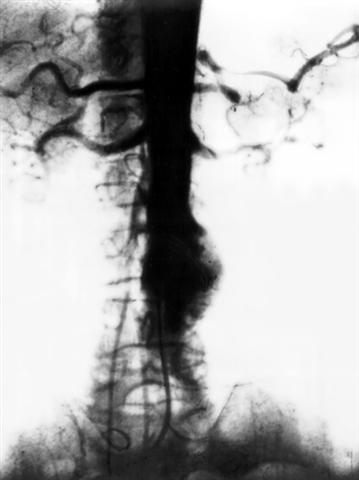

Рис. 2. Аортограмма при аневризме брюшной части аорты.